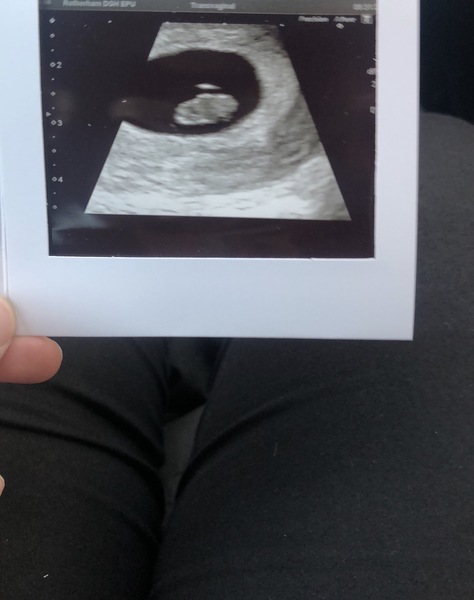

AIDE2424 · 27/12/2018 20:06

All good here! What a relief! it was panicking even more as my symptoms have all but disappeared and I didn’t want to mention that on the thread incase it was bad news and it made anyone else worry! Here’s a photo! Measuring 9+2 ❤️